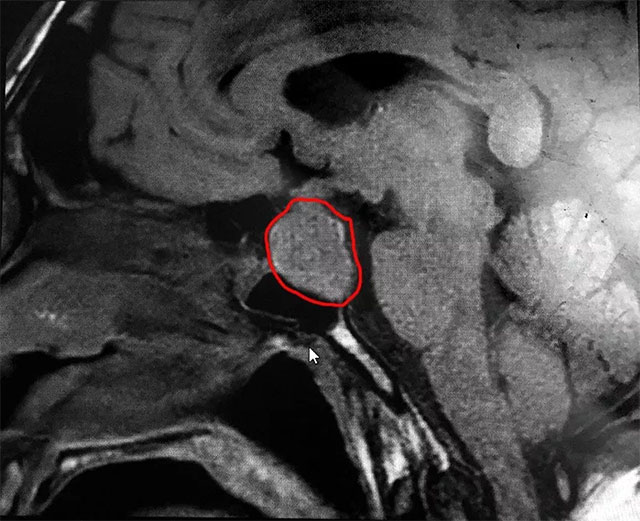

▲ 标记处为患者肿瘤部位

直到近两年,李先生感觉不对劲。他右侧手指开始发麻,走路也有些不稳;近一个多月,明显感觉自己右侧手指发麻加重,连筷子也拿不住了,四肢指关节也大得异常,他这才开始怀疑是不是患了什么疾病。

之后,李先生就诊于当地医院并进行颅脑CT检查。这不检查不知道,一检查吓一跳,原来是垂体瘤引起的远端肢体肥大,为了寻求进一步治疗,李先生慕名就诊于上海蓝十字脑科医院。